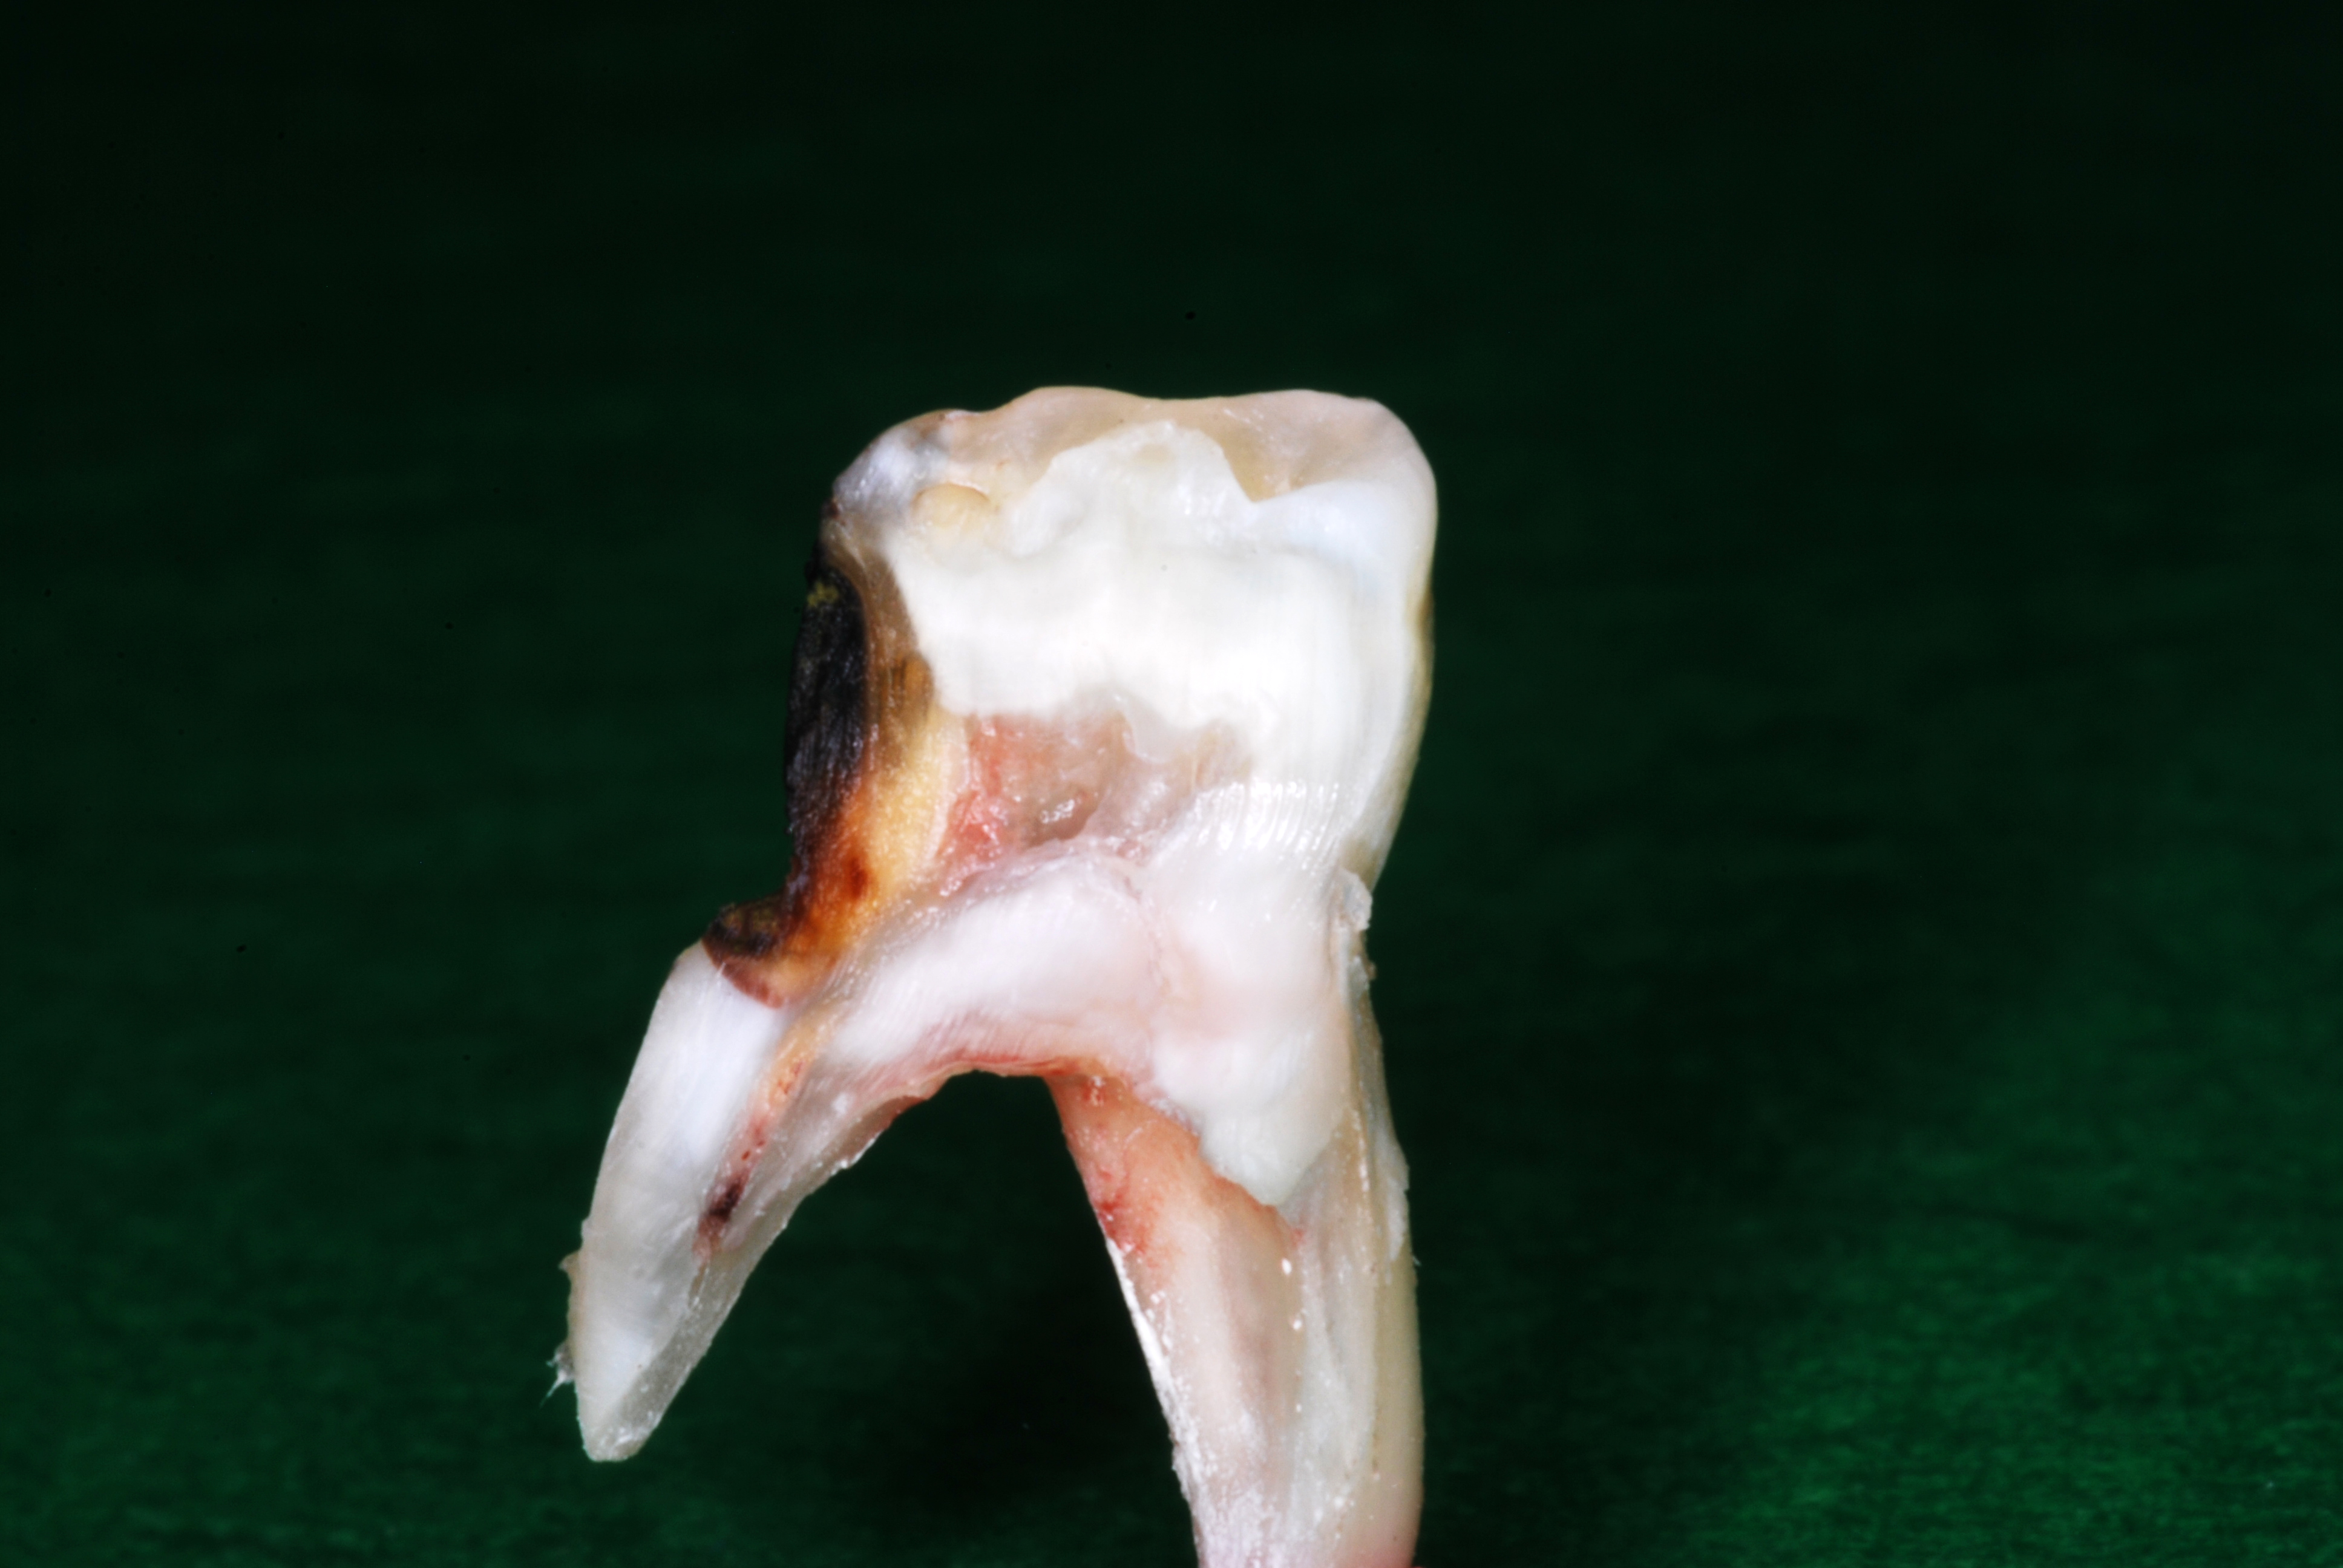

(1.) Hypocalcified/carious first molar, 12 months after SDF application.

Figure 1

(11.) Views of sectioned primary molar that was extracted for orthodontic considerations 22 months after three SDF treatments that were each 6 months apart.

Figure 11

(12.) Views of sectioned primary molar that was extracted for orthodontic considerations 22 months after three SDF treatments that were each 6 months apart.